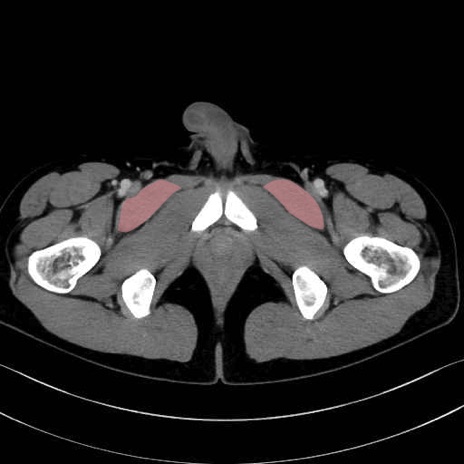

恥骨筋 (Pectineus)